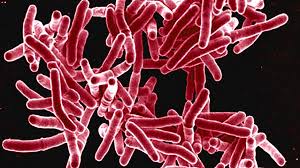

Светот и понатаму се соочува со една од најсмртоносните заразни болести. Според најновите податоци, во 2024 година од туберкулоза заболеле околу 10,7 милиони луѓе, додека 1,23 милиони починале, што ја потврдува туберкулозата како водечка причина за смрт од еден инфективен агенс во светски рамки. Истовремено, болеста и понатаму е глобален јавно-здравствен и социјален предизвик, особено во земјите со ниски и средни приходи.

Во Македонија, ситуацијата е релативно стабилна и земјата се смета за држава со низок ризик со околу 10 случаи на 100.000 жители. Според домашни податоци, годишно се регистрираат меѓу 130 и 160 нови случаи, со смртност од 6 до 15 пациенти. Иако бројките се ниски во споредба со глобалниот товар, експертите предупредуваат дека болеста не исчезнува и дека останува присутна и кај млади и кај урбани популации.

Според Светската здравствена организација, туберкулозата останува една од водечките причини за смртност во светот. Организацијата активно ги координира глобалните напори за рано откривање, лекување и превенција, како и за имплементација на нови препораки и терапии.

Туберкулозата не е само медицински, туку и социјален проблем. Ризикот значително се зголемува кај лица со ослабен имунитет (на пример лица со ХИВ), неухранетост, дијабетес и употреба на тутун и алкохол.

Особено ранливи се популациите во сиромашни и пренатрупани услови за живеење, каде што преносот на инфекцијата е полесен.